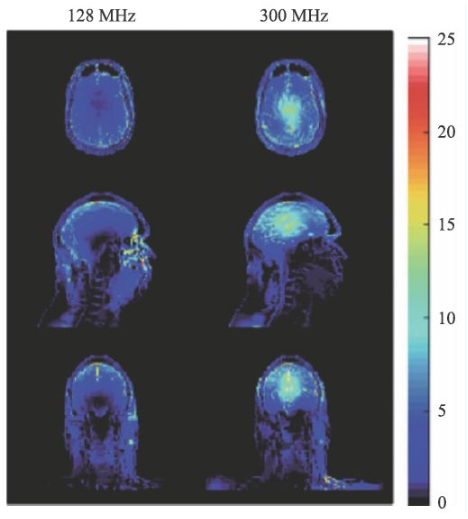

圖14 是一個(gè)SAR值對(duì)大腦溫度升高的一個(gè)仿真結(jié)果[14],對(duì)于平均SAR=3 W/kg的頭部掃描,7 T(右側(cè))下的溫度升高顯著高于3 T(左側(cè))。因此在超高M(jìn)RI中均需要配置一個(gè)可靠的SAR值監(jiān)控裝置。

圖14 局部SAR值的仿真結(jié)果